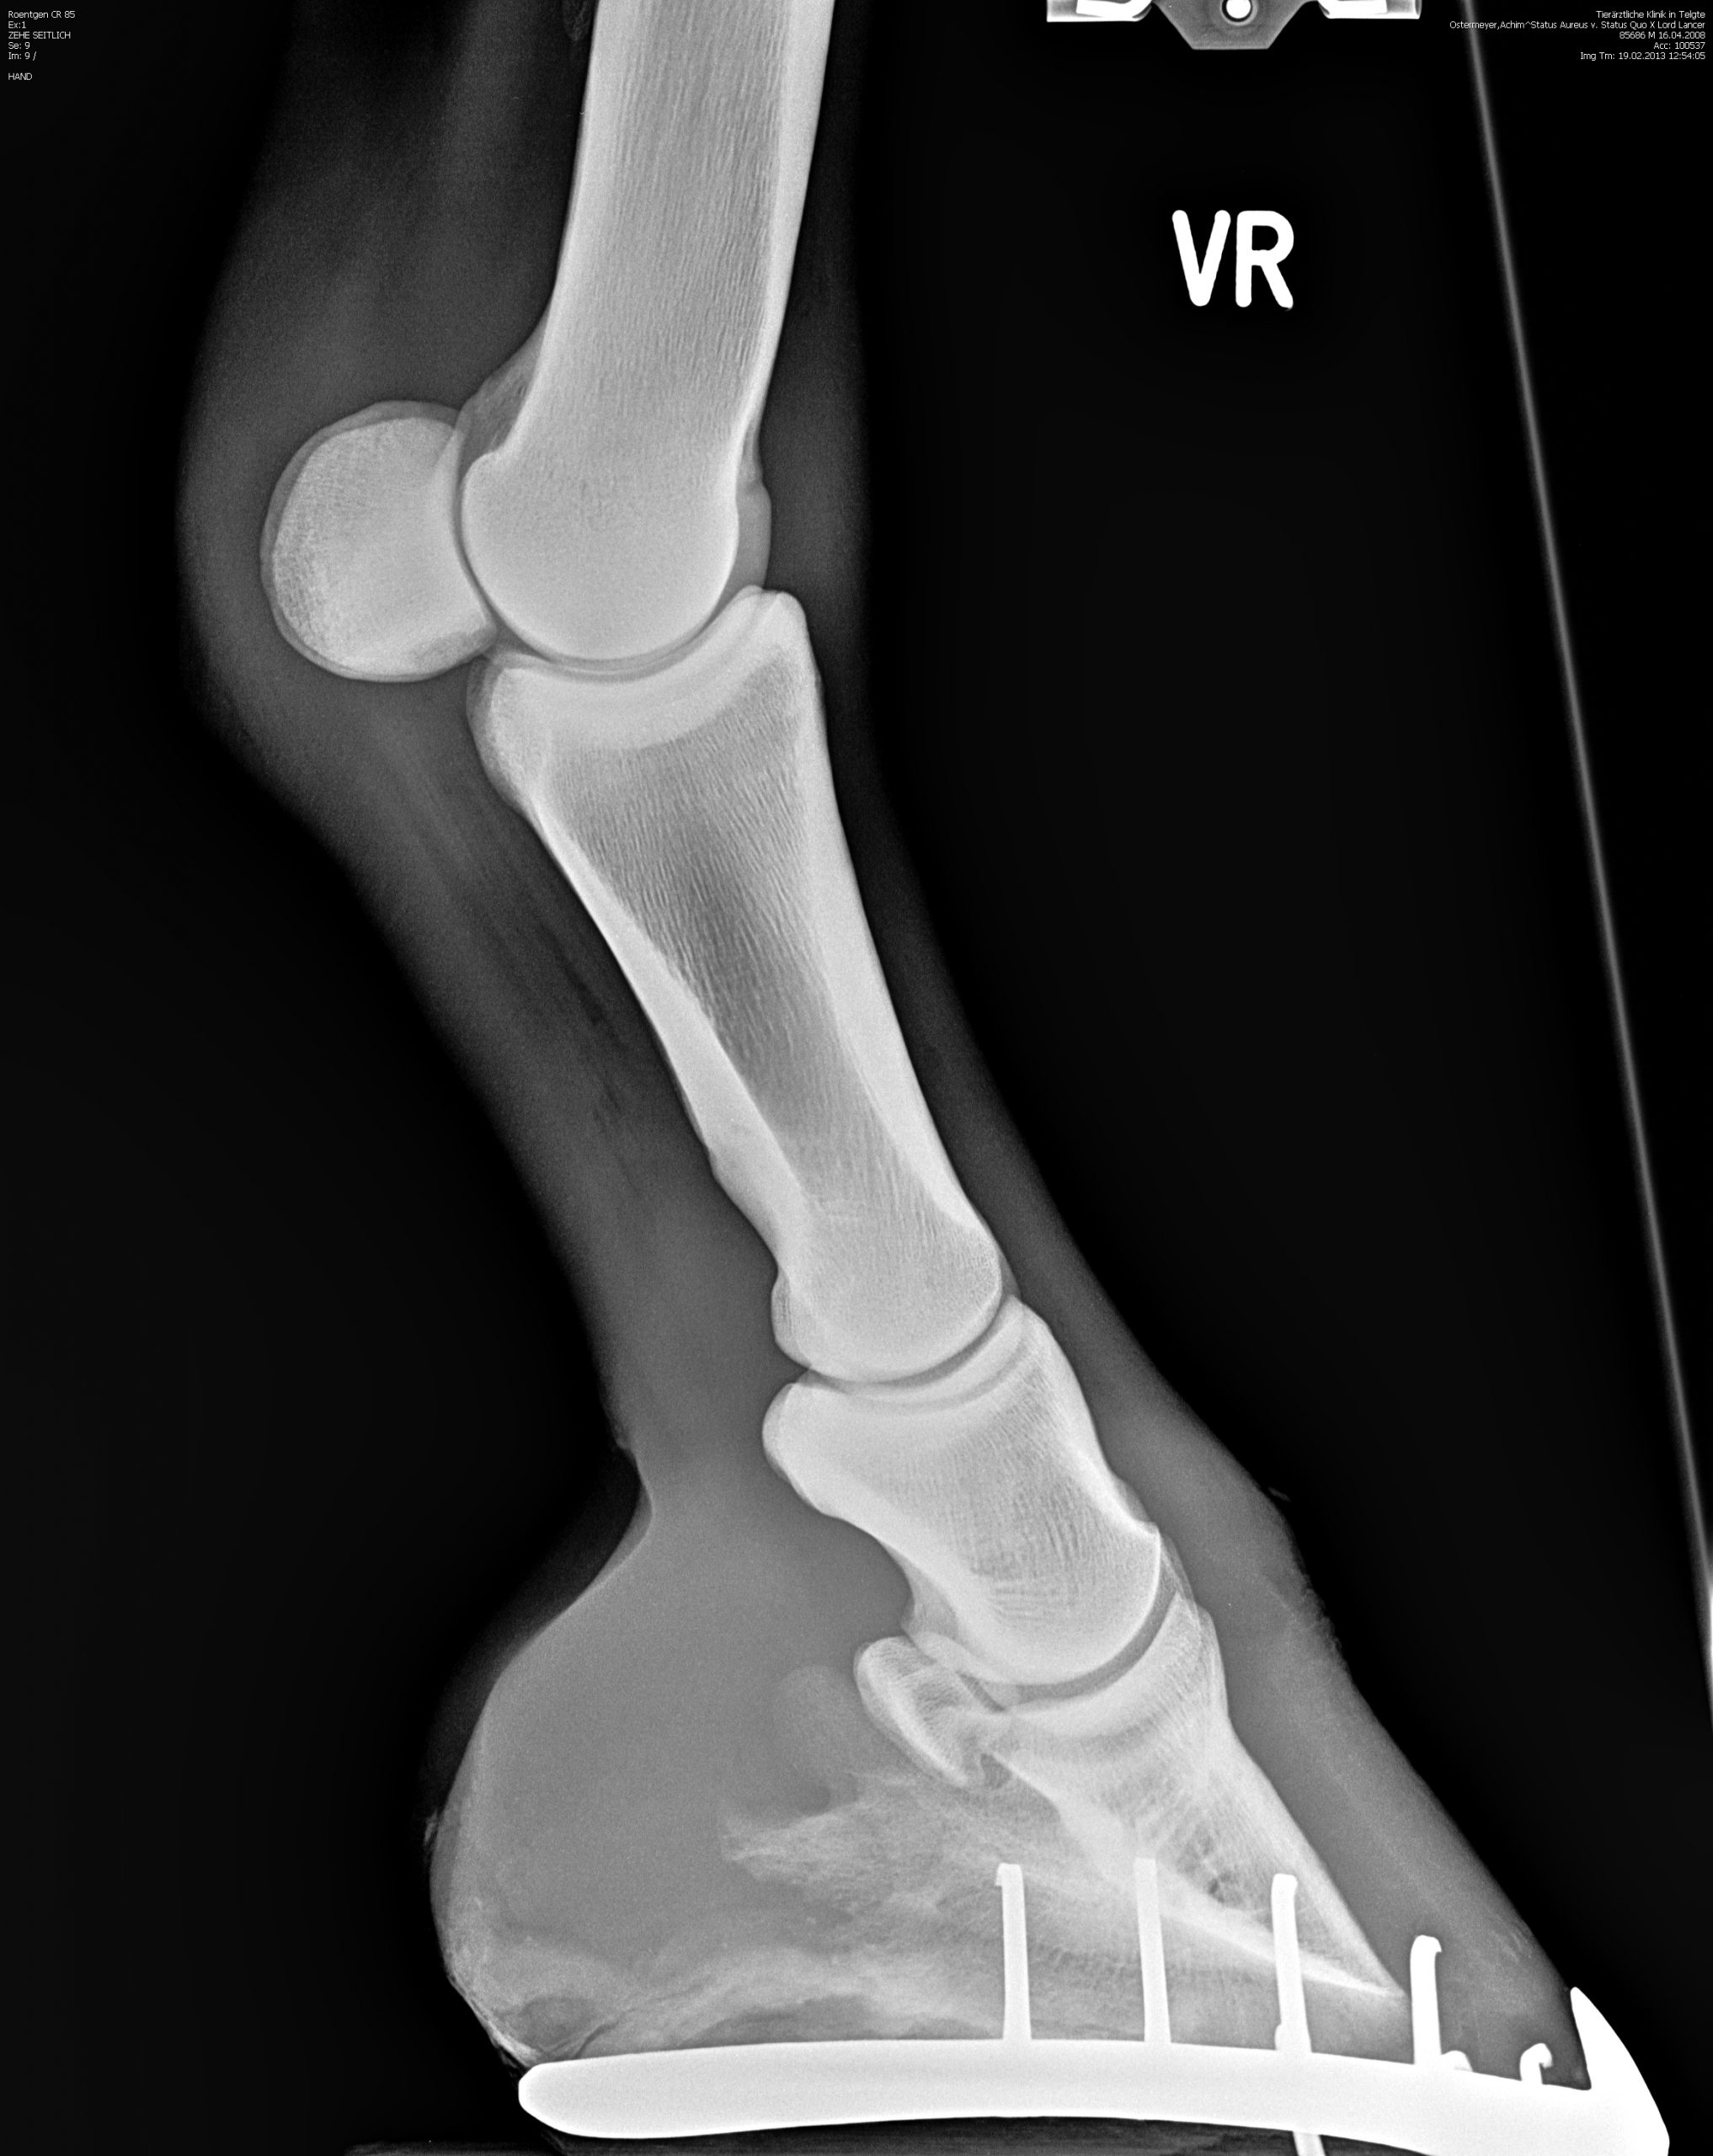

Röntgenbilder

Diese Sammlung zeigt verschiedene Röntgenaufnahmen, die eine Vielzahl von anatomischen Strukturen und potenziellen Gesundheitszuständen veranschaulichen. Jede Aufnahme bietet wertvolle Einblicke in die Gesundheit und das Wohlbefinden Ihrer Pferde.